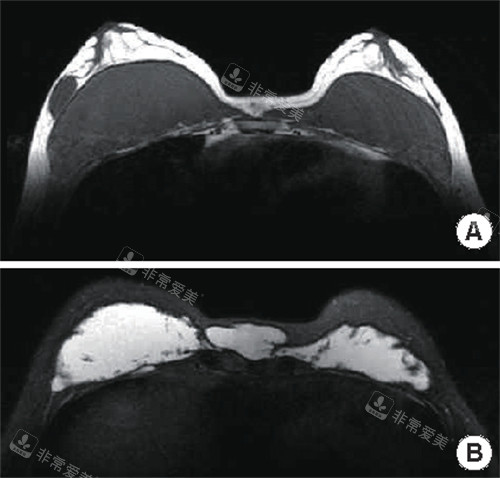

采用0.02mm精度的磁共振影像重建技术,结合智能导航系统(误差<0.1mm),对生长因子、非法注射物的分布区域进行精又准标记,完全避免传统手术“盲取”导致的遗漏问题。

术前通过3D超声或CT扫描构建三维模型,让求美者直观了解异物分布与手术方案,同时为术中操作提供精又准导航,提升手术可靠性与有效性。